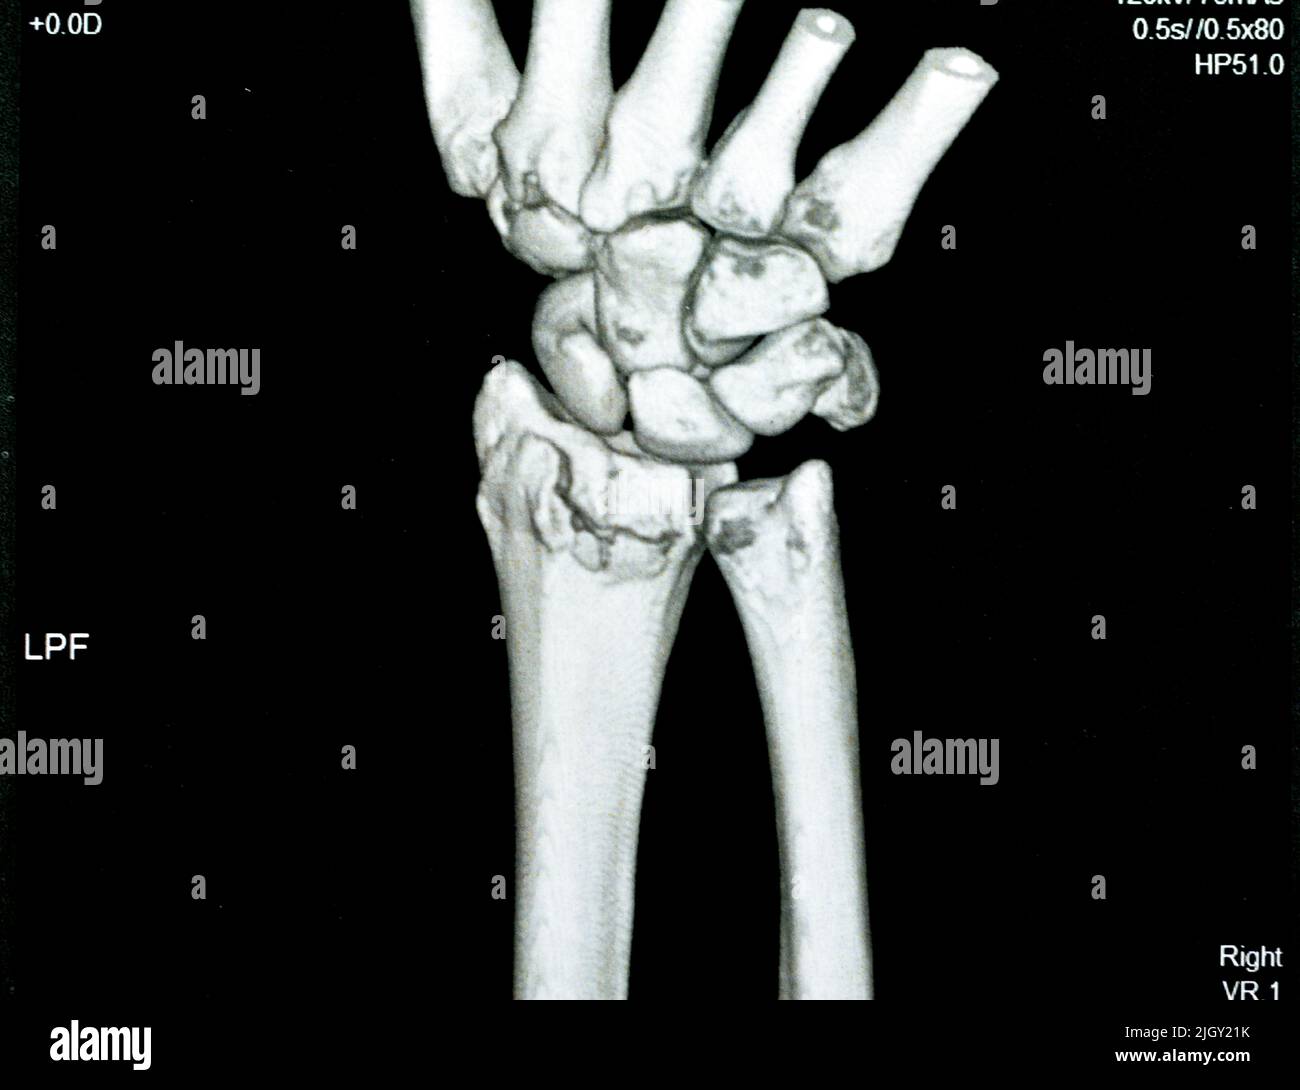

Prepare to be captivated by Top, a showcase of x ray of right hand and wrist imagery powered by wonderkidsmontessori.edu.vn. More related visuals are below.

x ray of right hand and wrist

Posts: x ray of right hand and wrist